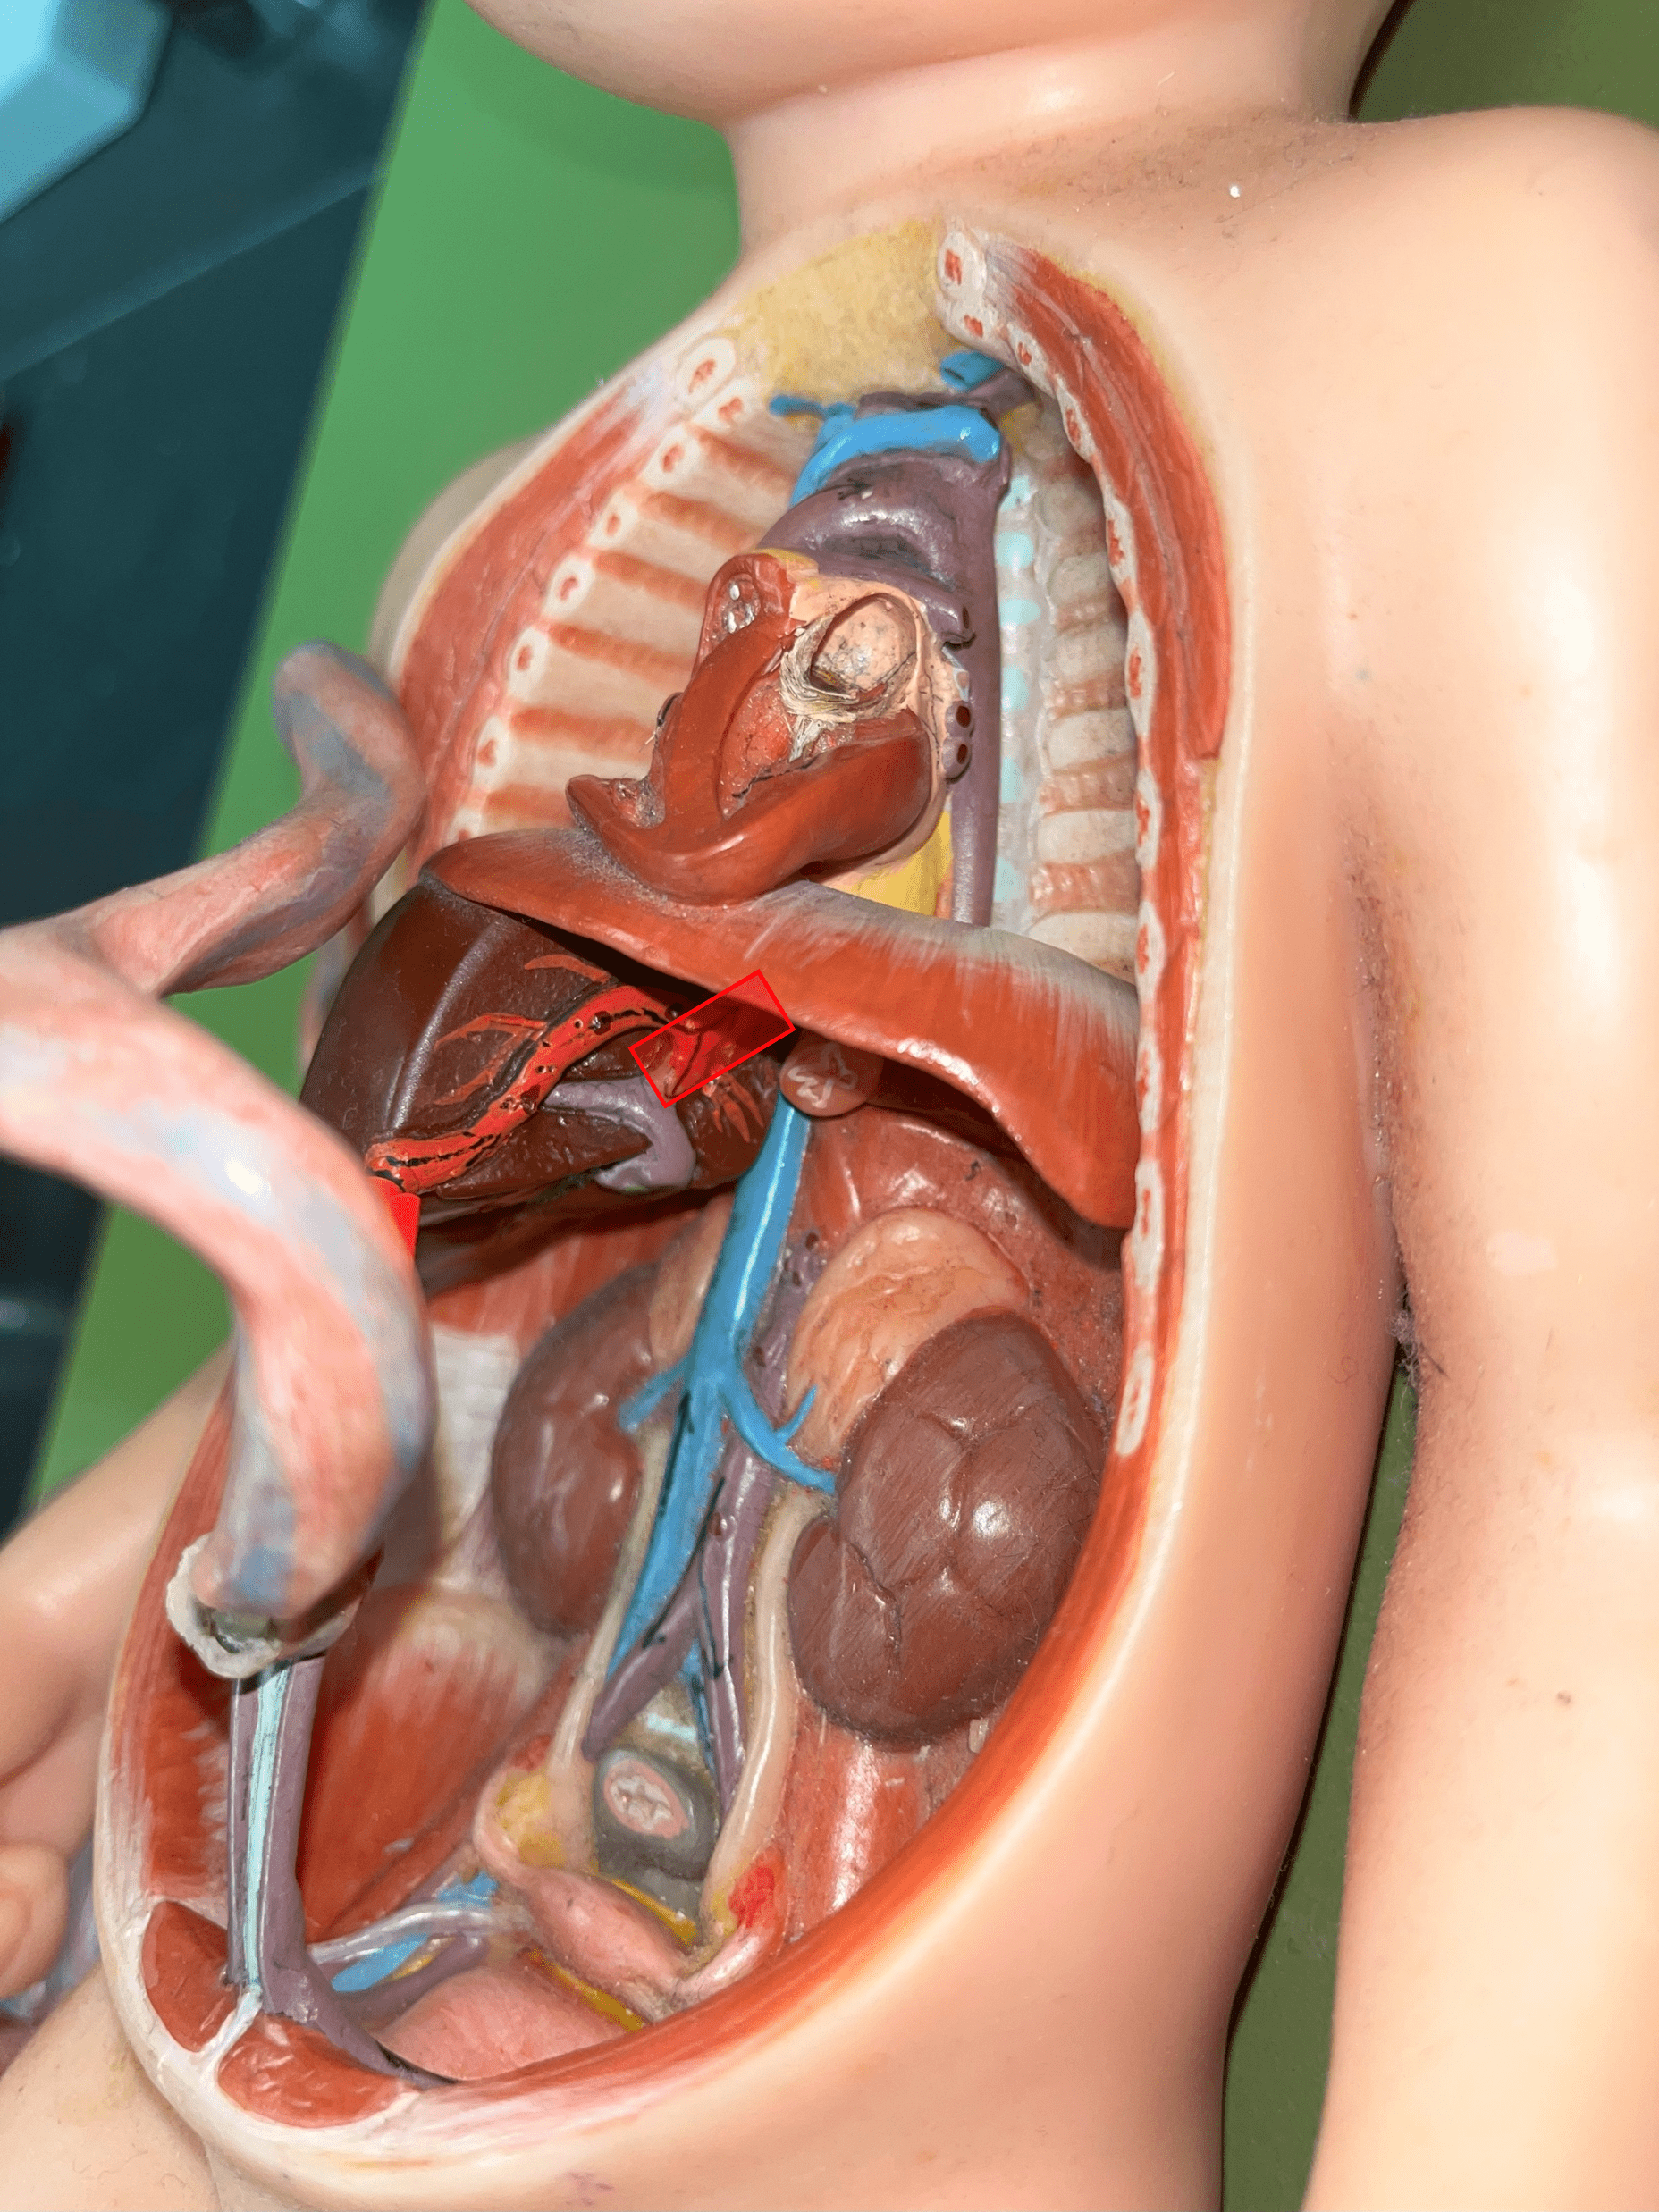

ductus venosus

• Part of the fetal circulation.

• Shortcuts blood to the inferior vena cava, bypassing the liver.

• Becomes the ligamentum venosum.

• Shortcuts blood to the inferior vena cava, bypassing the liver.

• Becomes the ligamentum venosum.